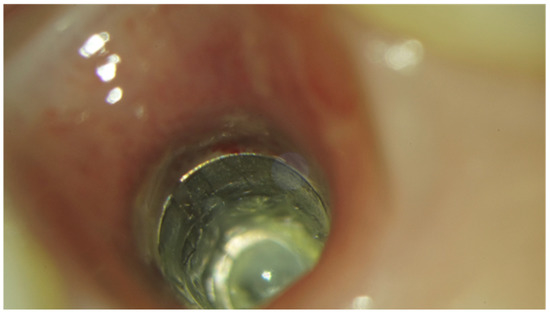

- Velásquez-Plata, D.; Lutonsky, J.; Oshida, Y.; Jones, R. A close-up look at an implant fracture: A case report. Int. J. Periodontics Restor. Dent. 2002, 22, 483–491. [Google Scholar]